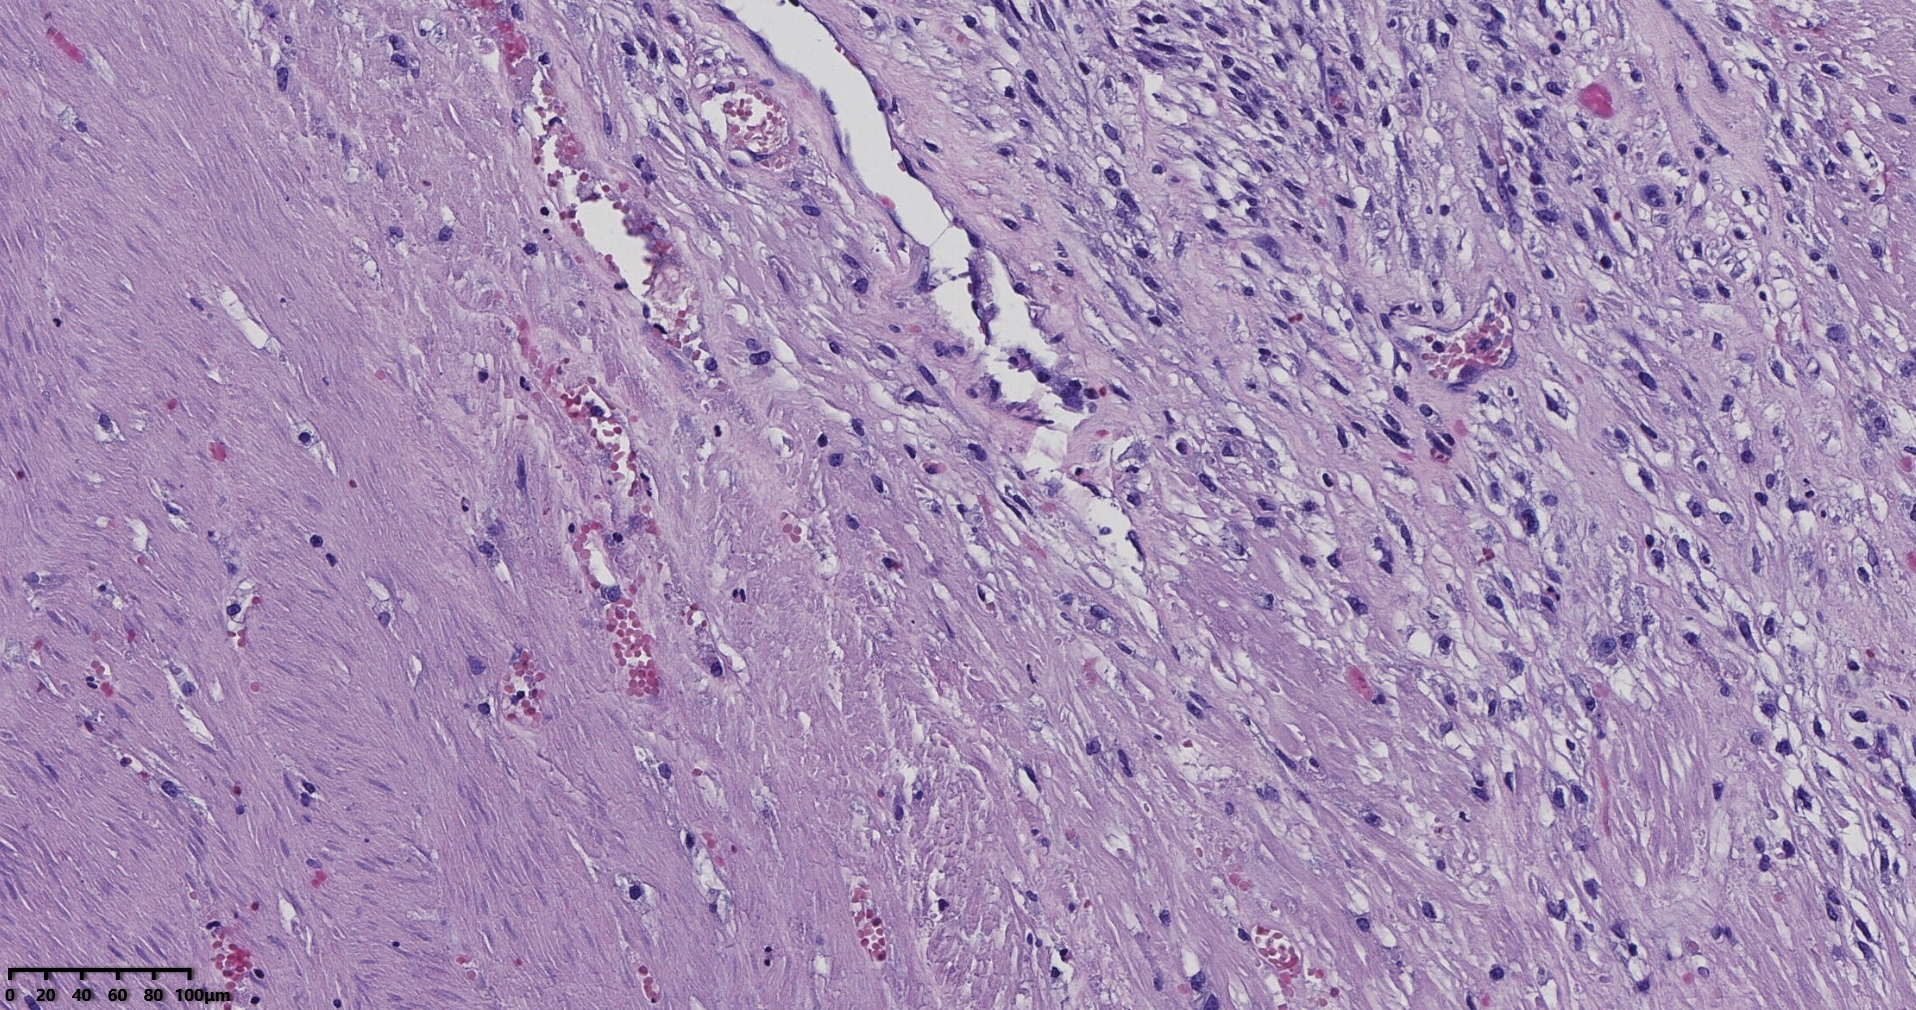

送检灰白肿物十余个,直径多在2-3厘米,切面均为灰白、实性,质地韧,其中一个大肿物,直径约7厘米,切片灰白灰红,质地韧当时取材时印象还是平滑肌瘤,伴变性,不考虑肉瘤,因为形态规整,质地韧,不脆,切面灰白,不是灰黄。

镜下所见小肿物无特殊,大肿物瘤细胞密集,中心区有变性、坏死,瘤细胞核有异型性。大肿物补充取材,发现,部分区域切面灰黄,这个区域,瘤细胞更密集,异型性更显著。肿物边缘有薄层正常平滑肌组织被覆,靠近边缘瘤细胞最密集,局部瘤组织内小血管较丰富。